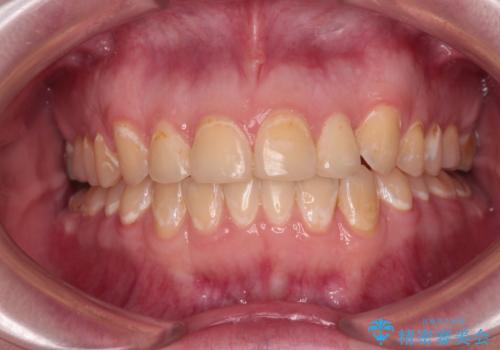

舌側転位している側切歯特有の、切縁の位置が不揃いであったり、根元が内側に引っ込んだ状態であったりという、インビザライン独特の仕上がりになることなく、きれいに整った歯列とすることができました。